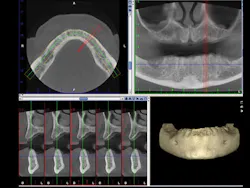

Diagnosis and treatment for third-molar impactions is reported to be the second most frequent use of cone beam. CR Foundation surveys show that more than 50% of GPs remove impacted third molars. It is well known that third-molar removal is one of the most frequent techniques that is challenged legally. Can you tell where the roots of a third molar are located? Are the roots facial or lingual to the inferior alveolar canal? If you break off a root tip, where is it located in a 3-D orientation? Two-dimensional radiographs are extremely helpful in many situations, but 3-D views as shown in Figure 3 add highly useful views in many dimensions, including facial-lingual, more predictability, and a better clinical result.

Figure 3: An example cone beam image shows in the upper right image the typical 2-D view of the maxilla and mandible. The lower left image shows the maxilla and mandible view 90 degrees from the upper right image. Planning for implant placement is greatly improved by cone beam images.